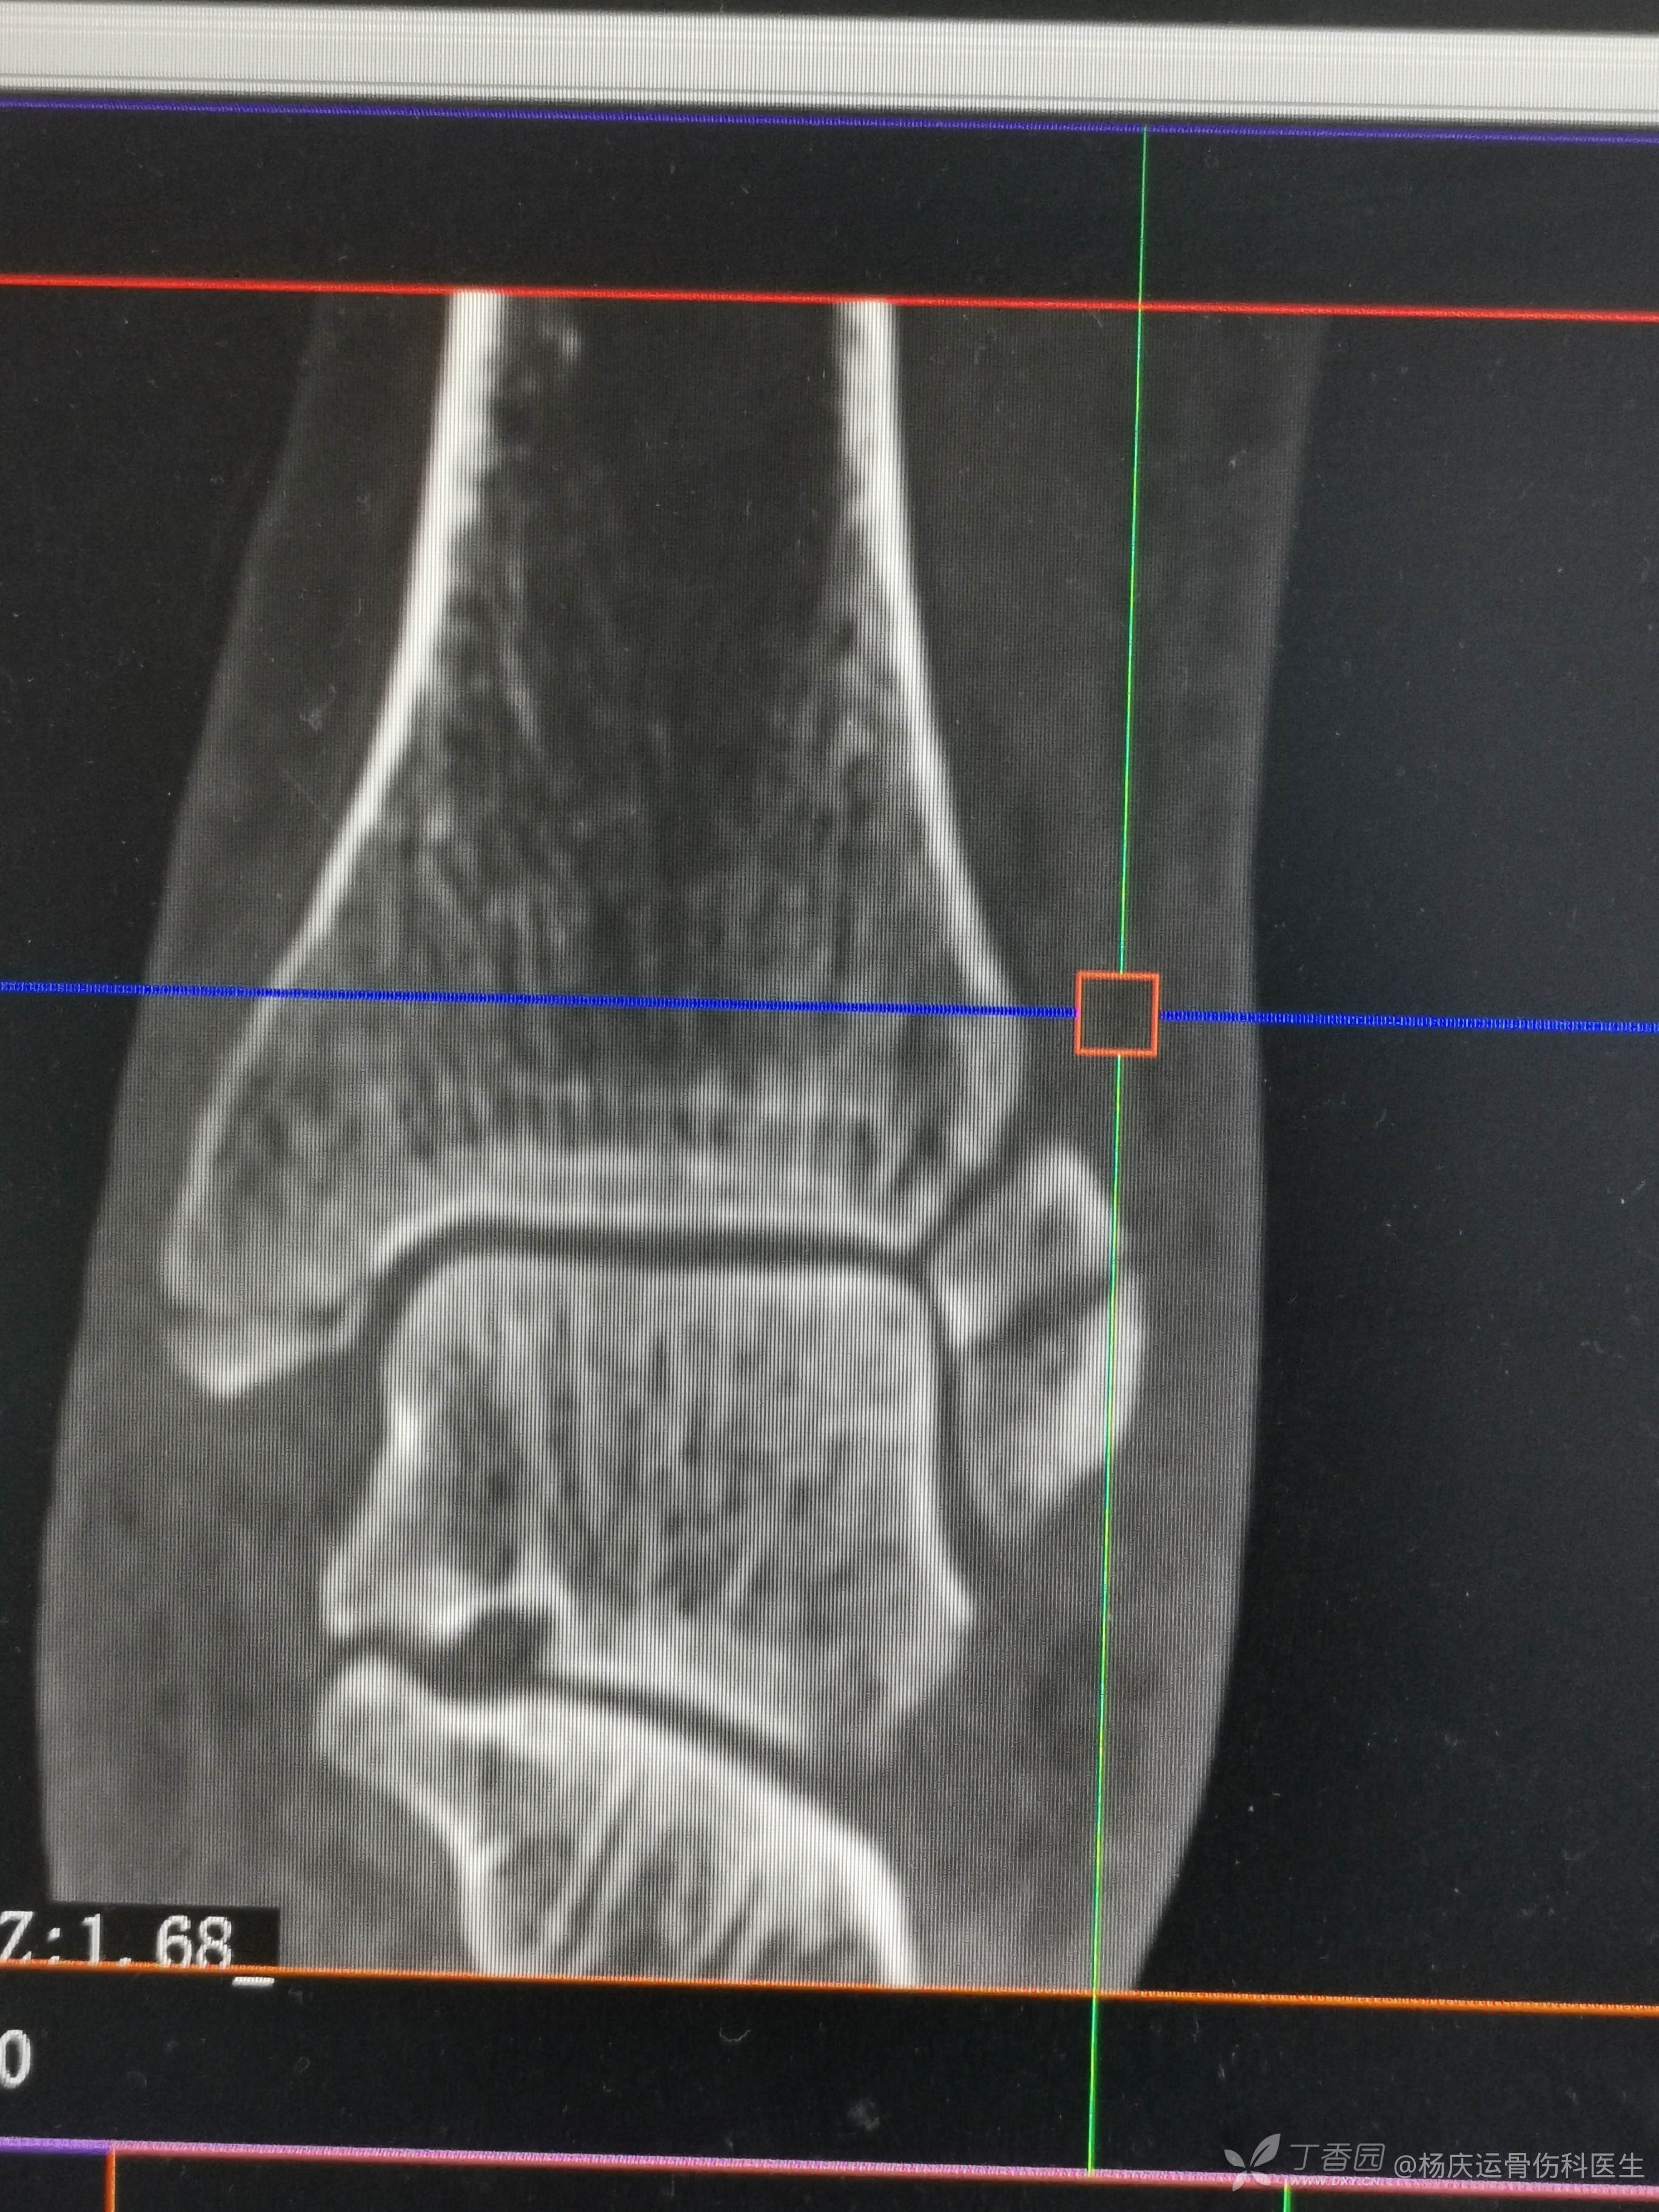

复位前CT